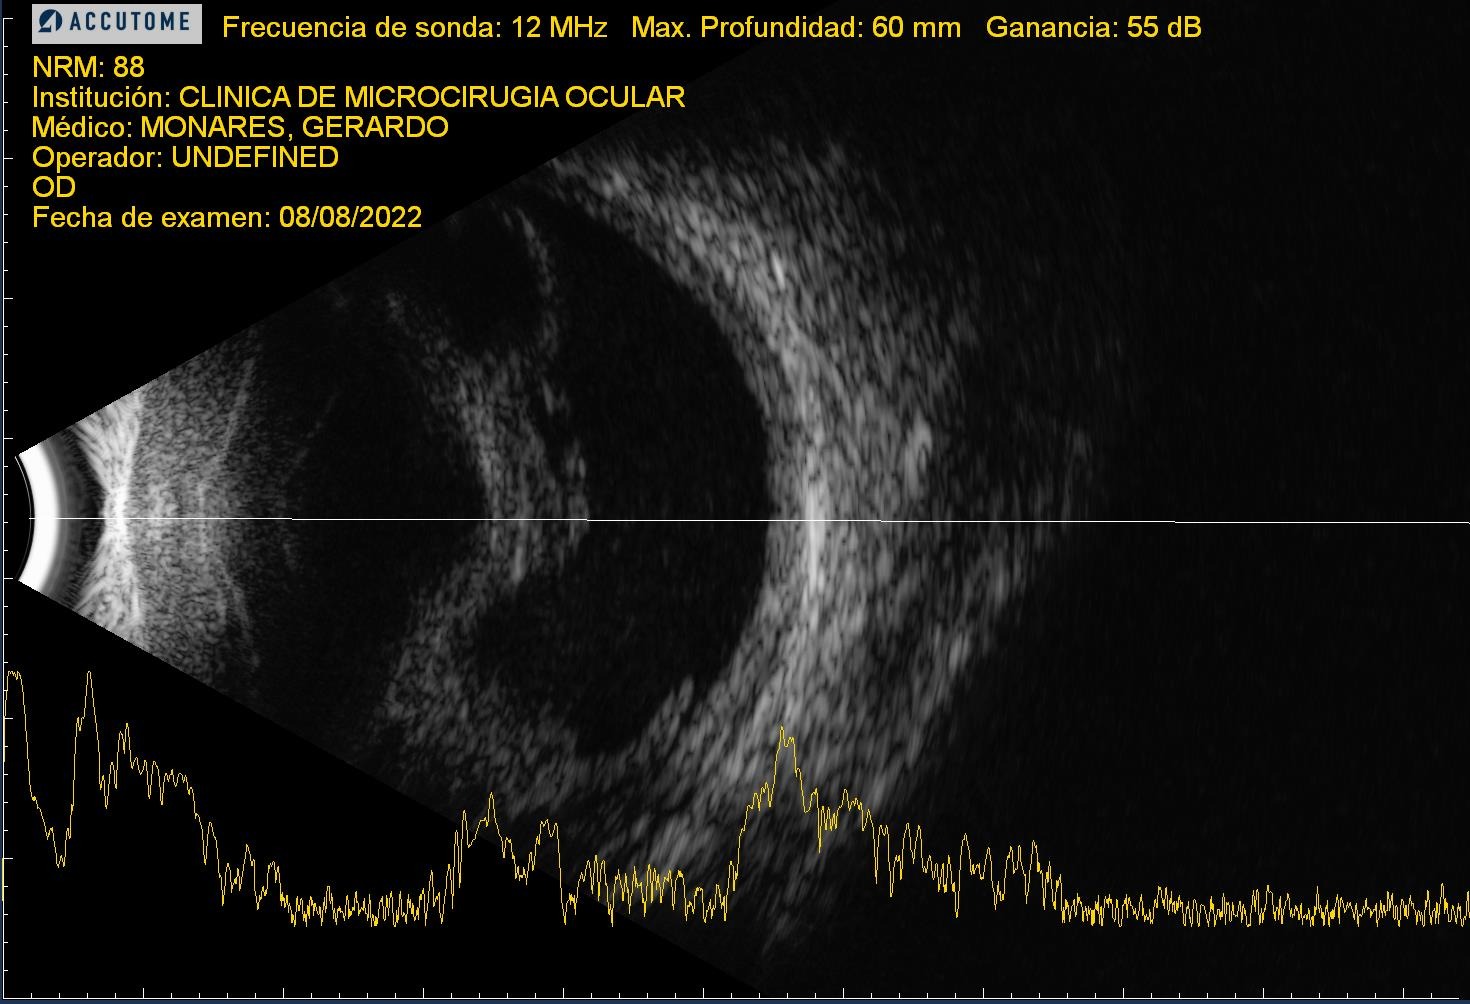

| RDP HV o HS | ![]() ![]() ![]() | ![]() ![]() ![]() | Normal o EMD | Normal o engrosamiento coroideo | ![]() | CIRUGIA: Vitrectomía + Endolaser | H Vítrea H Subhialoidea |

| RDP DRT | ![]() | ![]() | ![]() | ![]() | CIRUGIA: Vitrectomía + Endolaser + Silicón | Tracción sobre todo macular | |